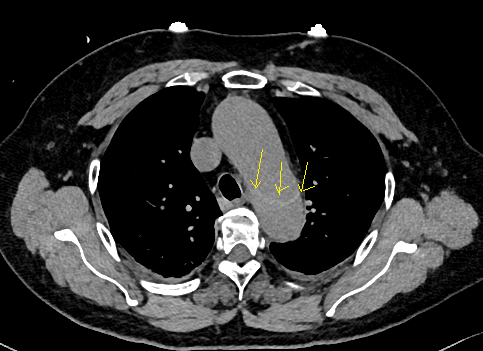

下图的胸部CT平扫,有什么致命的问题?

仔细一看,主动脉里面有线样阴影!并且,线样阴影两边的密度一高一低!

增强CT一看,主动脉夹层,密度相对高的是流动的血液!